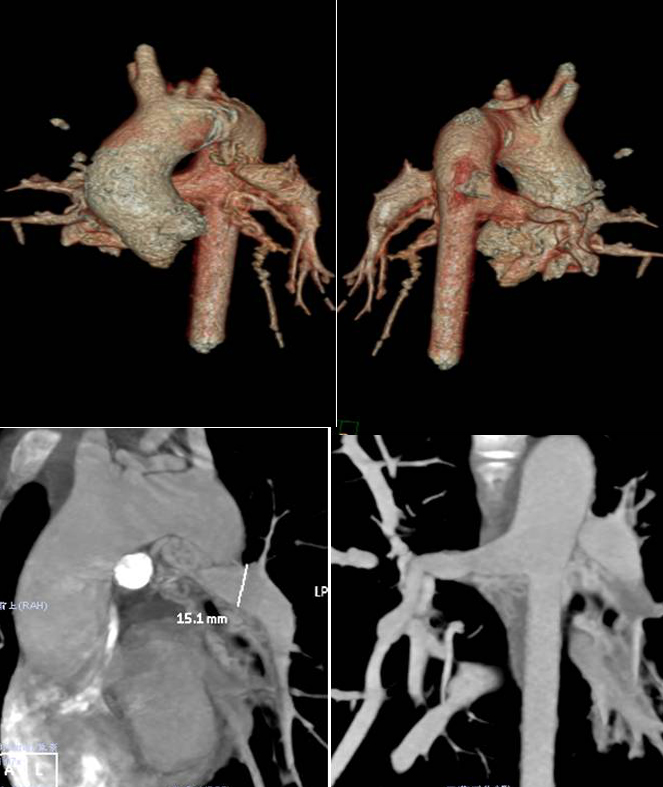

术前的评估,准确分型十分关键,尤其是术前行心脏CT检查,经过病房的前期准备,患儿于122日上午来到CT室,资深的扫描技术人员针对该复杂先心病的种类、患者年龄、循环状态评估,提前设计好了扫描方案,随后在双源FLASH CT上成功完成扫描,由经验丰富的诊断医师对图像解读并做出专业的图像后处理,提交外科,纠正了术前极终诊断:先天性心脏病,肺动脉闭锁(IV型),室间隔缺损,粗大侧支循环形成;异常走行左无名静脉。